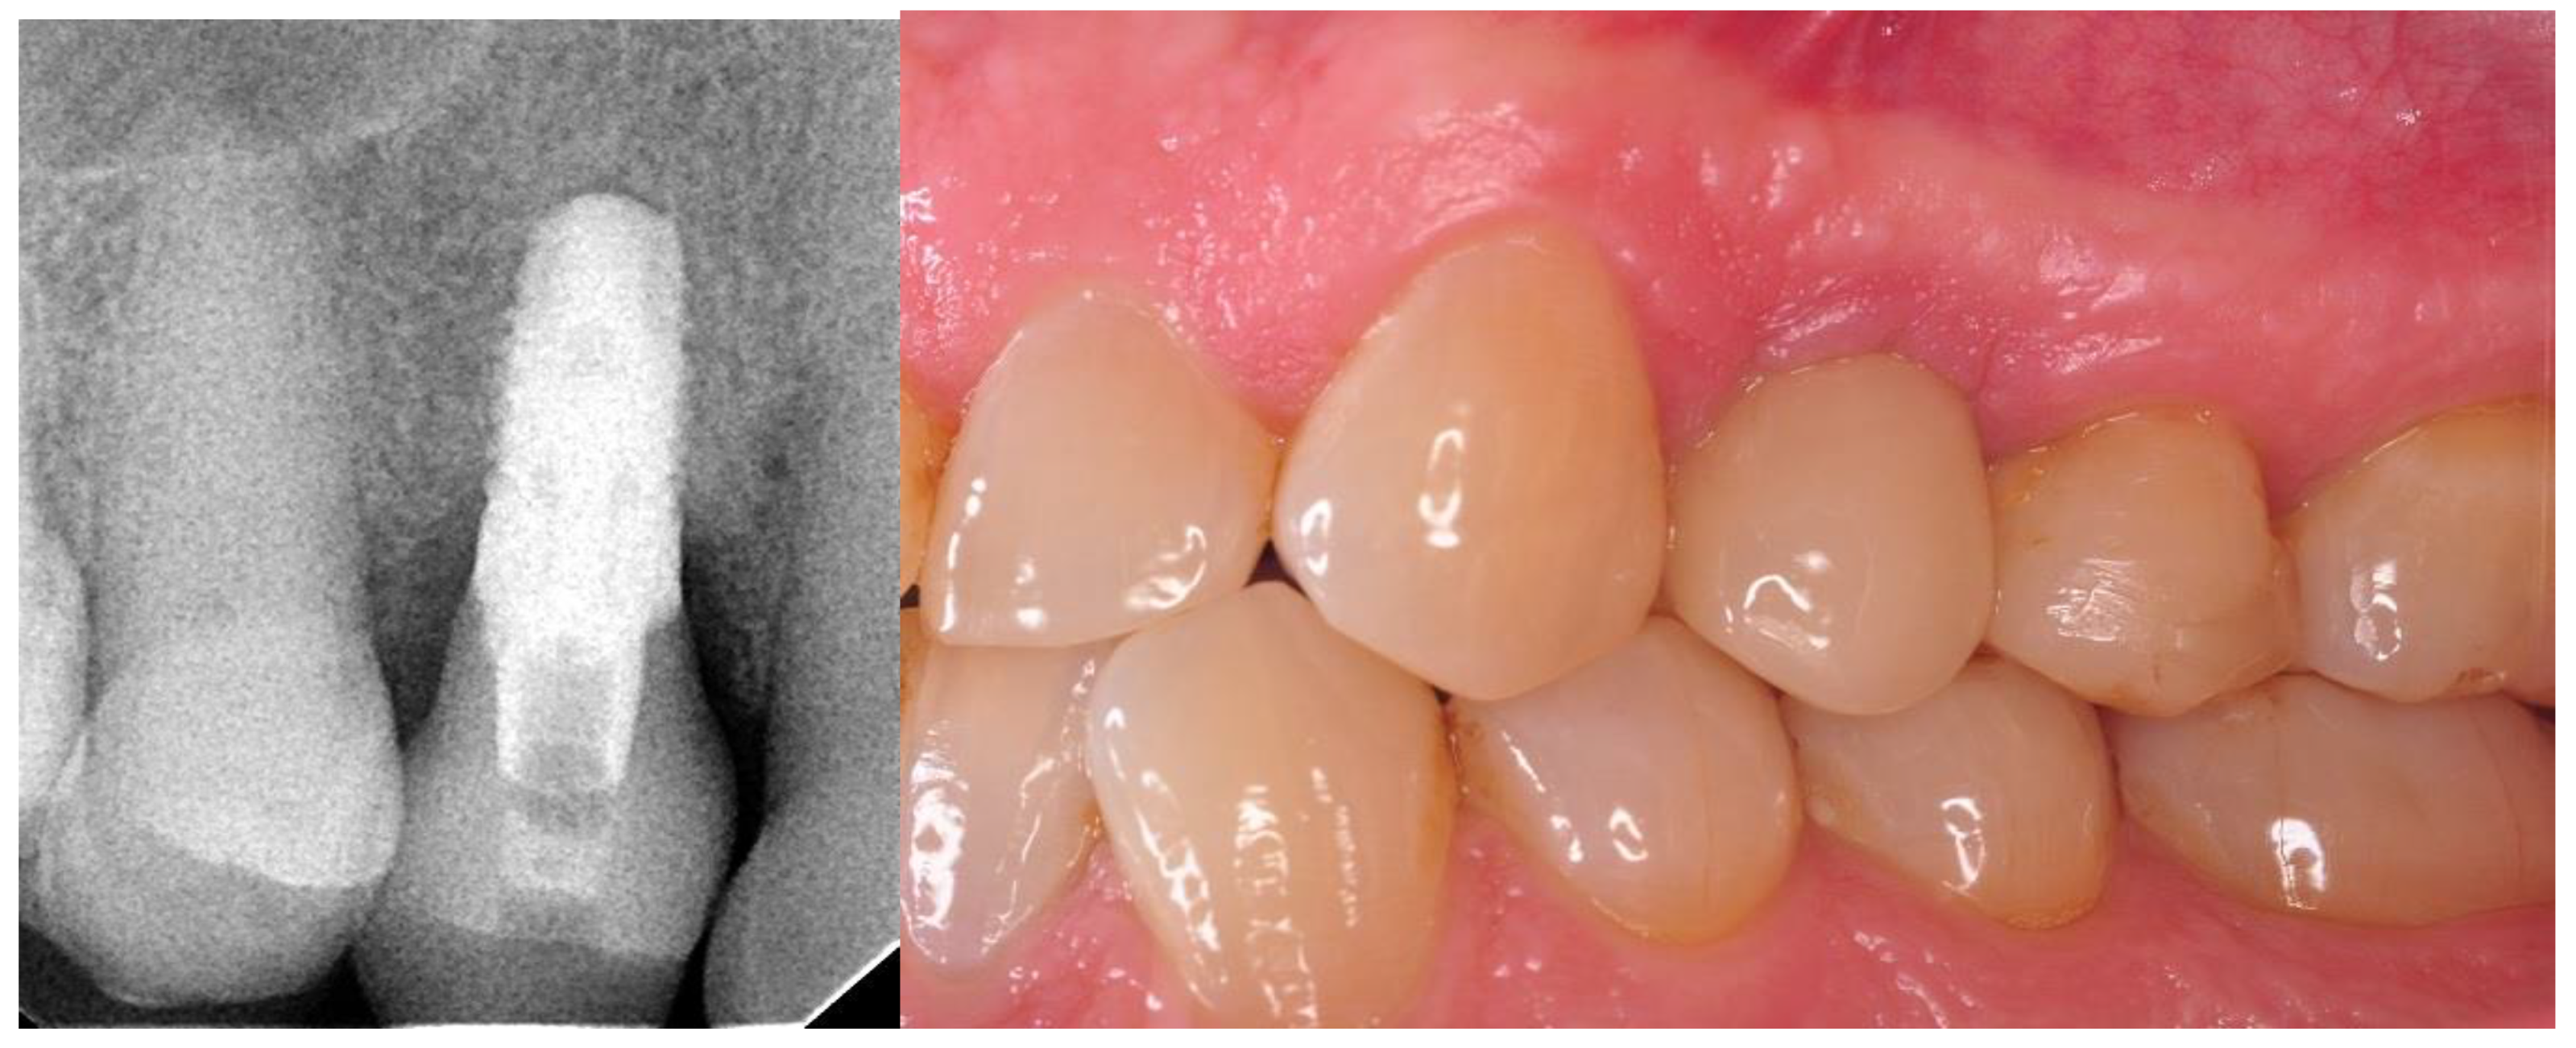

- Twelve months after the surgery: clinical evaluation (HKT, probing pocket depth (PPD), Visual Analogue Scale (VAS), pink esthetic score (PES) and white esthetic score (WES)) and radiological assessment (RVG and CBCT).

3.4. Results of Aesthetic Evaluation

3.5. Results of VAS Score